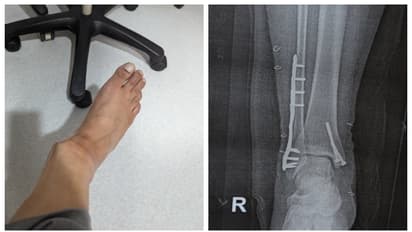

"ഓഗസ്റ്റ് 14 ന് പുലർച്ചെ ചെന്നൈയിൽ നിന്നുള്ള ഇൻഡിഗോ വിമാനത്തിൽ ഞാൻ ദില്ലിയിലെ ടി 2 ൽ എത്തി. അവരിൽ ഏറ്റവും സാധാരണമായതുപോലെ, എയറോബ്രിഡ്ജ് നൽകിയിട്ടില്ല, പകരം എല്ലാവരോടും അവരുടെ റാമ്പുകൾ ഉപയോഗിച്ച് ഇറങ്ങാൻ ആവശ്യപ്പെട്ടു," അദ്ദേഹം എഴുതി. മഴയുണ്ടായിരുന്നതിനാല് യാത്രക്കാര്ക്ക് ഉപയോഗിക്കാന് നല്കിയ റാമ്പ് നനഞ്ഞിരുന്നു. ഈർപ്പം കാരണം പാതിവഴിയെത്തിയപ്പോള് തന്റെ വലതു കാൽ റാമ്പിലെ ഈർപ്പമുള്ള ഭാഗത്തേക്ക് വഴുതി. പിന്നാലെ താഴെ വീണു. ഒന്നെങ്കില് കണങ്കാല് ഒടിയുകയോ സ്ഥാനം മാറുകയോ ചെയ്തതായി അപ്പോള് തന്നെ തനിക്ക് തോന്നിയതായും അദ്ദേഹം കുറിച്ചു. സഹയാത്രികരുടെ സഹായത്തോടെയാണ് താന് അവിടെ നിന്നും എഴുന്നേറ്റത്. ആ അപകടത്തിന് ശേഷമുള്ള വളഞ്ഞിരിക്കുന്ന കാലിന്റെ പടം പങ്കുവച്ച് കൊണ്ട് രത്നേന്ദു റേ എഴുതി.

ഇൻഡിഗോ ജീവനക്കാർ വീൽചെയറിൽ കിടത്തി ടെർമിനലിലെ ക്ലിനിക്കിലേക്ക് കൊണ്ടുപോയി. പരിശോധനയില് കണങ്കാല് തകർന്നതായി കണ്ടെത്തി. എയർസേവ പോർട്ടലിൽ പരാതി രജിസ്റ്റർ ചെയ്തെങ്കിലും മറ്റാരും വഴുതി വീണിട്ടില്ലാത്തതിനാല് റാമ്പ് നനഞ്ഞിരുന്നില്ലെന്നും താന് തന്നെ വഴുതി വീണതാണെന്നുമായിരുന്നു ഇൻഡിഗോയുടെ പ്രതികരണം. ഇത് തനിക്ക് അപമാനമായി തോന്നിയെന്നു അദ്ദേഹം കുറിച്ചു. തനിക്ക് ശരിക്കും നടക്കണമെങ്കില് ഇനി കുറഞ്ഞത് ഒരു വര്ഷമെങ്കിലും എടുക്കും. വലത് കണങ്കാലിൽ ഒരു പ്ലേറ്റും സ്ക്രൂകളുമുണ്ട്, ചെറിയ ചലന ശേഷി മാത്രം. രണ്ട് ശസ്ത്രക്രിയകളുടെ പാടുകൾ, ഫിസിയോതെറാപ്പിക്കും ദിനചര്യയ്ക്കുമായി ഇപ്പോള് ഒരു വാക്കറിനെ ആശ്രയിക്കുകയാണെന്നു അദ്ദേഹം എഴുതി.